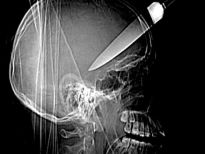

Şoke eden röntgen filmleri

Bu röntgen filmleri görenleri şaşkına çeviriyor!